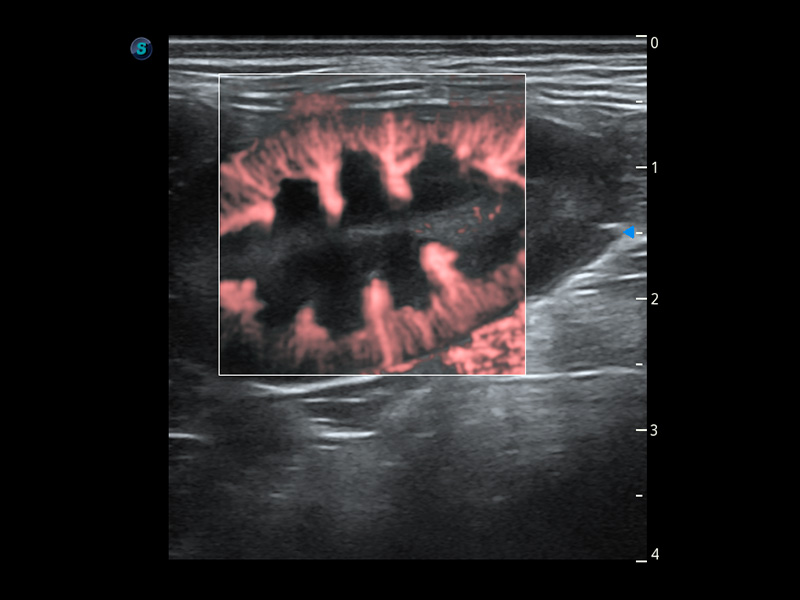

(猫)髂动脉血流频谱